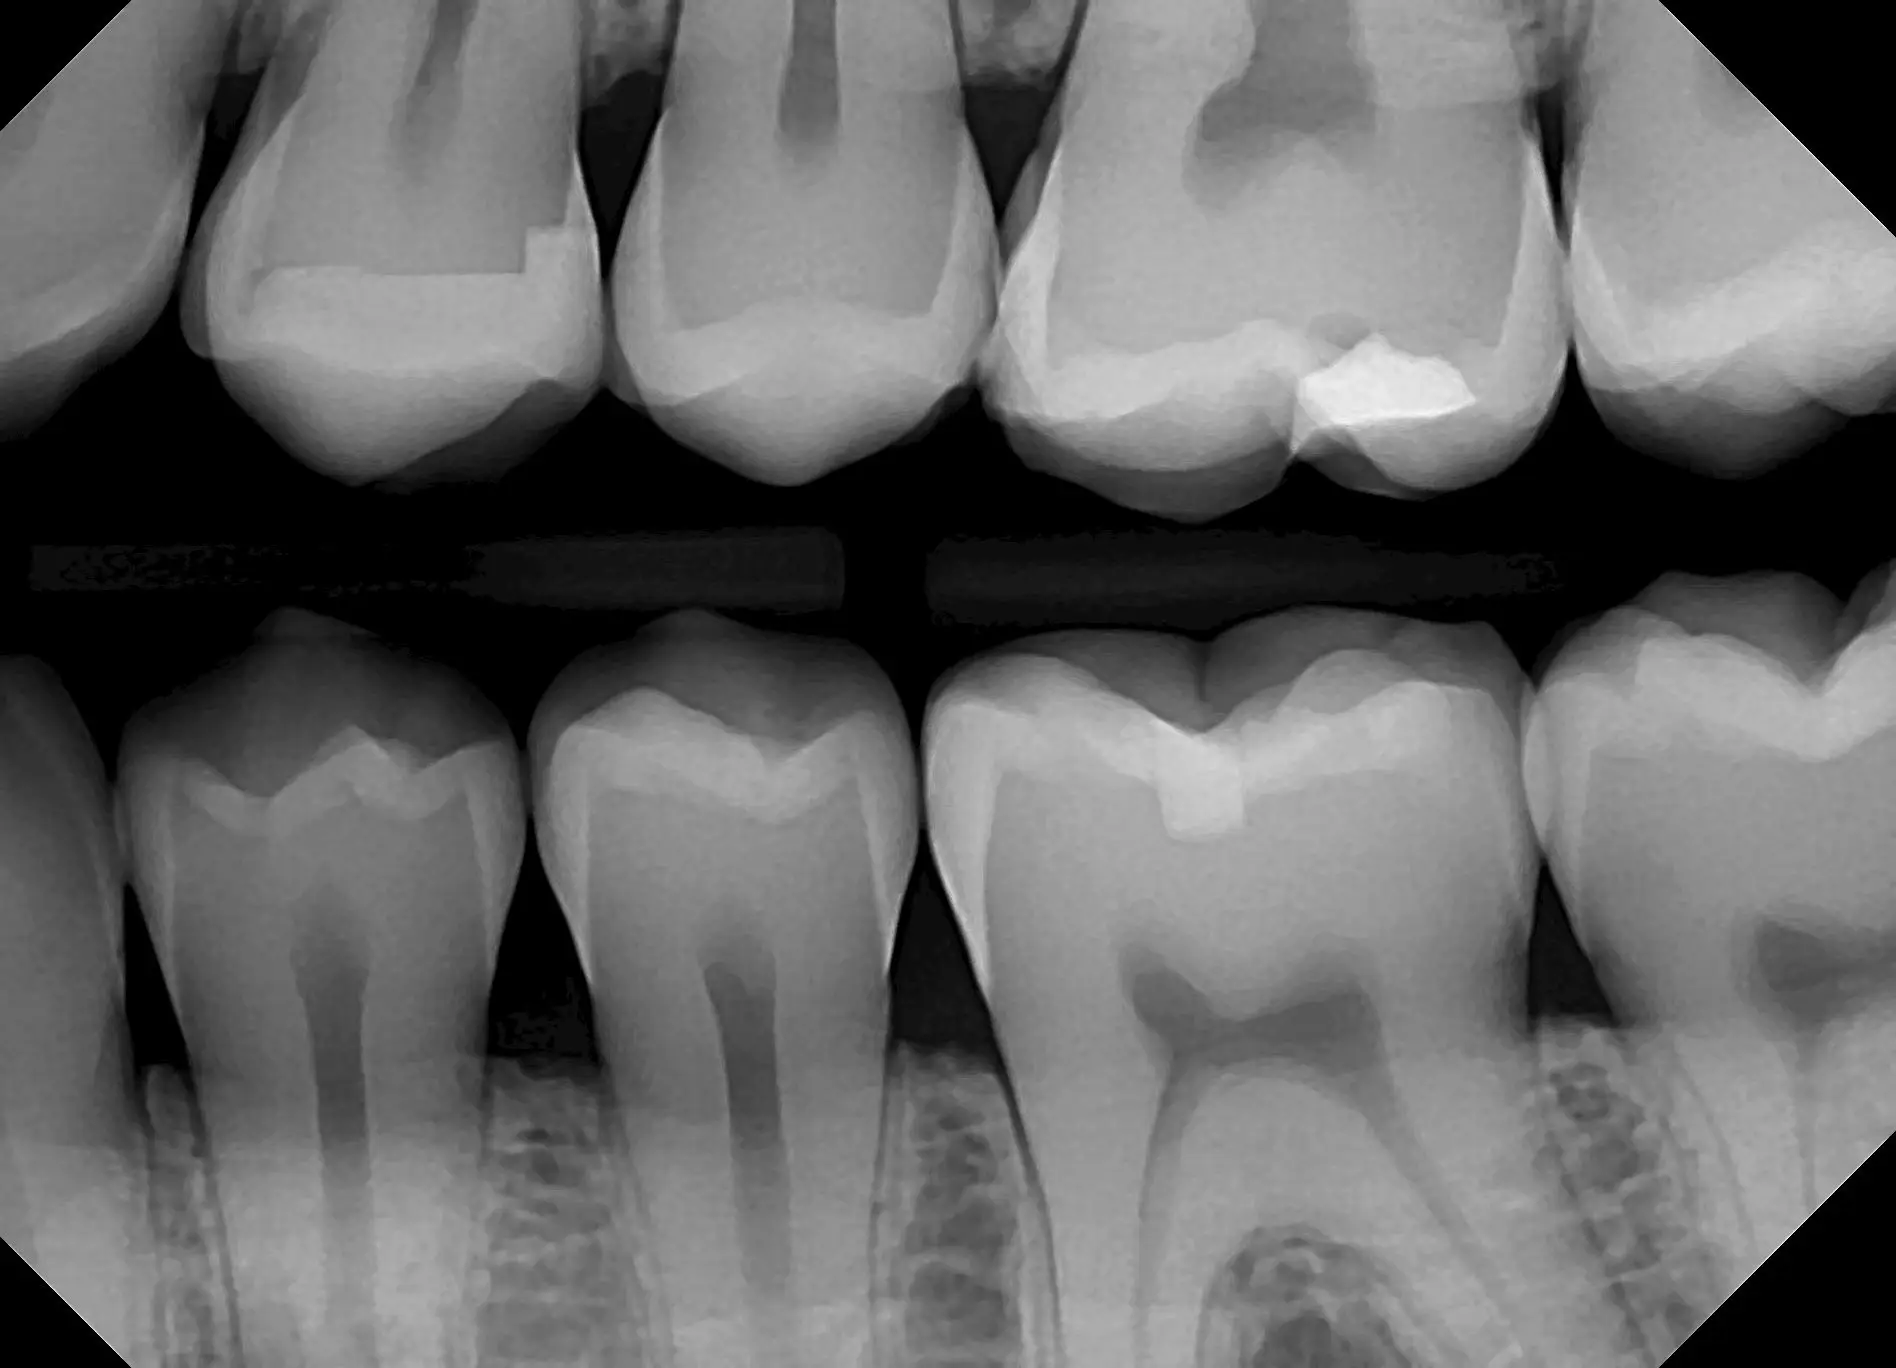

See for yourself the X-ray Gallery from the Dream Sensor!

Click any image in the x-ray gallery below to see the full version.

All images are taken with the DentiMax Dream Sensor and are compatible with the DentiMax Imaging Software and most other imaging software on the market.